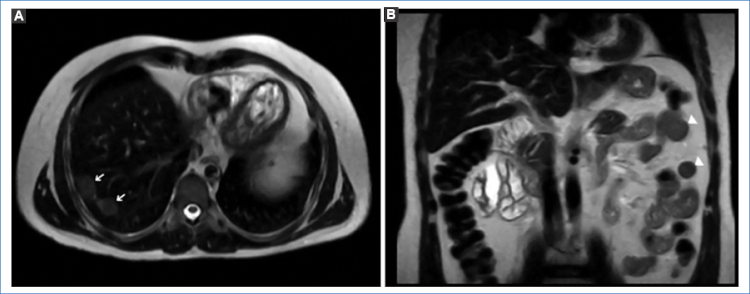

Se decide realizar una resonancia magnética (RM) para mejor caracterización de dichas lesiones, las cuales, junto con las observadas a nivel peritoneal ya descritas anteriormente como esplénulos por su estabilidad en el tiempo, son hipointensas en las secuencias ponderadas en T1, ligeramente hiperintensas en T2 y FATSAT, con tenue restricción de la difusión (DWI) y con similar realce tras la administración del contraste paramagnético (Figs. 2a4).

En los estudios de TC multidetector y RM, el tejido esplénico heterotópico tiene la misma apariencia e igual comportamiento que el bazo tras la administración del contraste endovenoso. En la TC sin contraste, la lesión es isodensa con respecto al parénquima hepático y presenta realce en fase arterial, difícil de diferenciar de un adenoma o un hepatocarcinoma4. En la RM, previo a la administración de contraste paramagnético, la lesión es homogéneamente hipointensa en las secuencias ponderadas en T1 e hiperintensas en las ponderadas en T2; después de la administración del gadolinio es hiperintensa en comparación con el resto del parénquima hepático1,5.